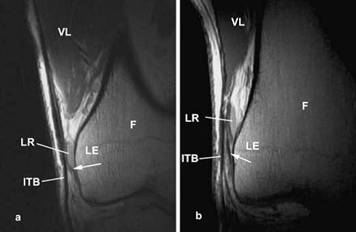

Głębsze włókna pasma biodrowo-piszczelowego są przytwierdzone do kłykcia bocznego za pomocą włóknistych pasemek, połączonych z powłoką silnie unerwionej tkanki tłuszczowej. Te głębsze pasma są powszechnie nazywane włóknami Kaplana i są przymocowane do wyniosłości noszącej nazwę guzka nadkłykciowego. Dzięki temu umocowaniu pasmo biodrowo-piszczelowe nie może ocierać się tam i z powrotem o guzek, co wynika ponownego przeanalizowania koncepcji tarcia jako przyczyny bólu. Przytwierdzenie zarówno do rzepki, jak i mięśnia dwugłowego uda w jeszcze większym stopniu zmniejsza ruchy przód/tył, gdy kolano się zgina i prostuje.

Zdjęcia rezonansu magnetycznego ukazujące włókniste pasma (oznaczone strzałkami) przytwierdzające pasmo do bocznego nadkłykcia (LE) kości udowej (F).